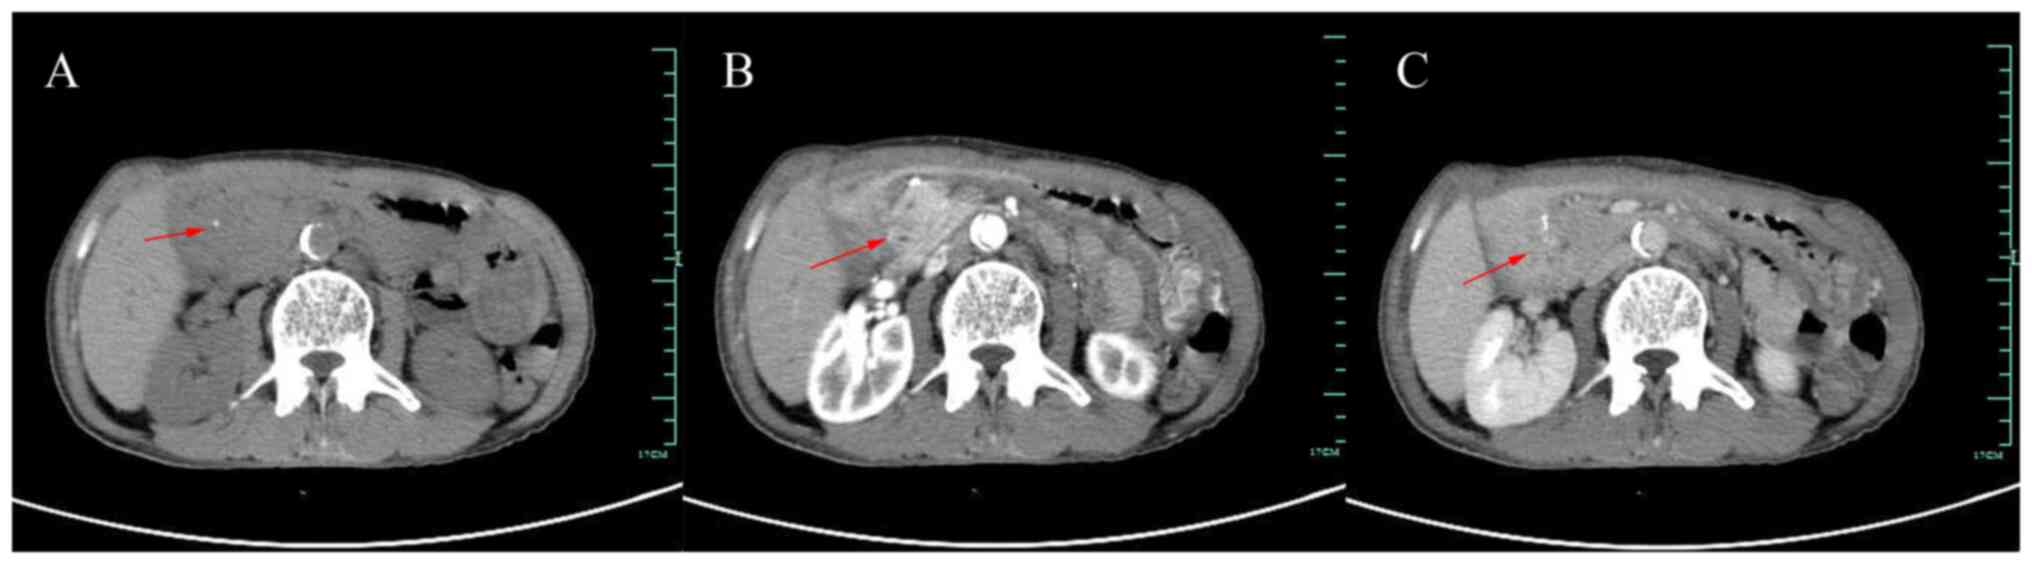

Magnetic resonance cholangiopancreatography of the patient showed mild dilatation of the bile duct and pancreatic duct, narrowing of the lower part of the common bile duct, no obvious occupancy and no abnormal signal in the pancreatic parenchyma. The contrast-enhanced CT of the abdomen showed patchy soft tissue density shadow in the pancreatic-gastroduodenal space with speckled calcification, poorly demarcated from the surrounding organs and no abnormal enhancement was seen. Additionally, the intra- and extra-hepatic bile ducts and pancreatic ducts were dilated (Fig. 3). We accessed the patient's endoscopic and imaging data at the time of hospitalization for hemorrhoid surgery 3 years before. At that time, the patient had no discomfort, CEA 8.04 ng/ml, ferritin 338.2 ng/ml and gastroscopy suggestive of duodenal erosion (recommended in combination with CT examination; Fig. 2B). No abnormalities were reported by the abdominal contrast-enhanced CT then but our review of the images revealed the presence of a lesion in the pancreaticoduodenal space at that time. For differential diagnosis, we refined tuberculin purified protein derivative test, T-spot, and the results were positive. Blood amylase and chest CT showed no abnormalities. Although there was no manifestation of pulmonary tuberculosis and the possibility of abdominal tuberculosis was small, rare cases could not be excluded. In addition, it was suggested to the patient to have a positron emission tomography computed tomography examination to exclude tumor disease, however the patient refused due to financial factors.

Figure 3

Contrast-enhanced CT. Contrast-enhanced CT disclosed a homogenously enhancing hypodense lesion between the pancreas and duodenum, with small cystic hypodense foci locally (red arrows). (A) Plain scan, (B) arterial phase, (C) delayed phase. CT, computed tomography.

On CT, the classic presentation of GP is a hypoenhancing slab-like hypodense soft tissue lesion in the middle of the pancreas and duodenum (7). Poor enhancement may be due to delayed circulation resulting from fibrous tissue hyperplasia and secondary stenosis of the arteries (18). Additionally, thickening of the duodenal wall and narrowing of the lumen may be observed, with cystic lesions often visible within the wall. In cases of segmental GP, mild dilation of the bile duct and pancreatic duct may be present and the lower portion of the common bile duct may be narrowed without evidence of vascular invasion (10,19). Unfortunately, early diagnosis of GP remains challenging through CT imaging. In the present case, the abnormalities in the groove area were overlooked by imaging specialists and clinicians three years earlier. Inflammatory changes in the groove region, thickening of the descending duodenal wall, and small cystic dilatations are crucial signs that should be emphasized. Early detection via CT provides prospective diagnostic value and can markedly guide treatment (7). Conservative management of patients with early-stage GP can often avoid unnecessary surgical procedures (16). In clinical practice, there remain instances wherein despite CT findings suggestive of inflammation and negative results from puncture pathology, clinicians encounter challenges in definitively excluding the prospect of malignant tumors. Consequently, they may opt for surgical intervention (10).